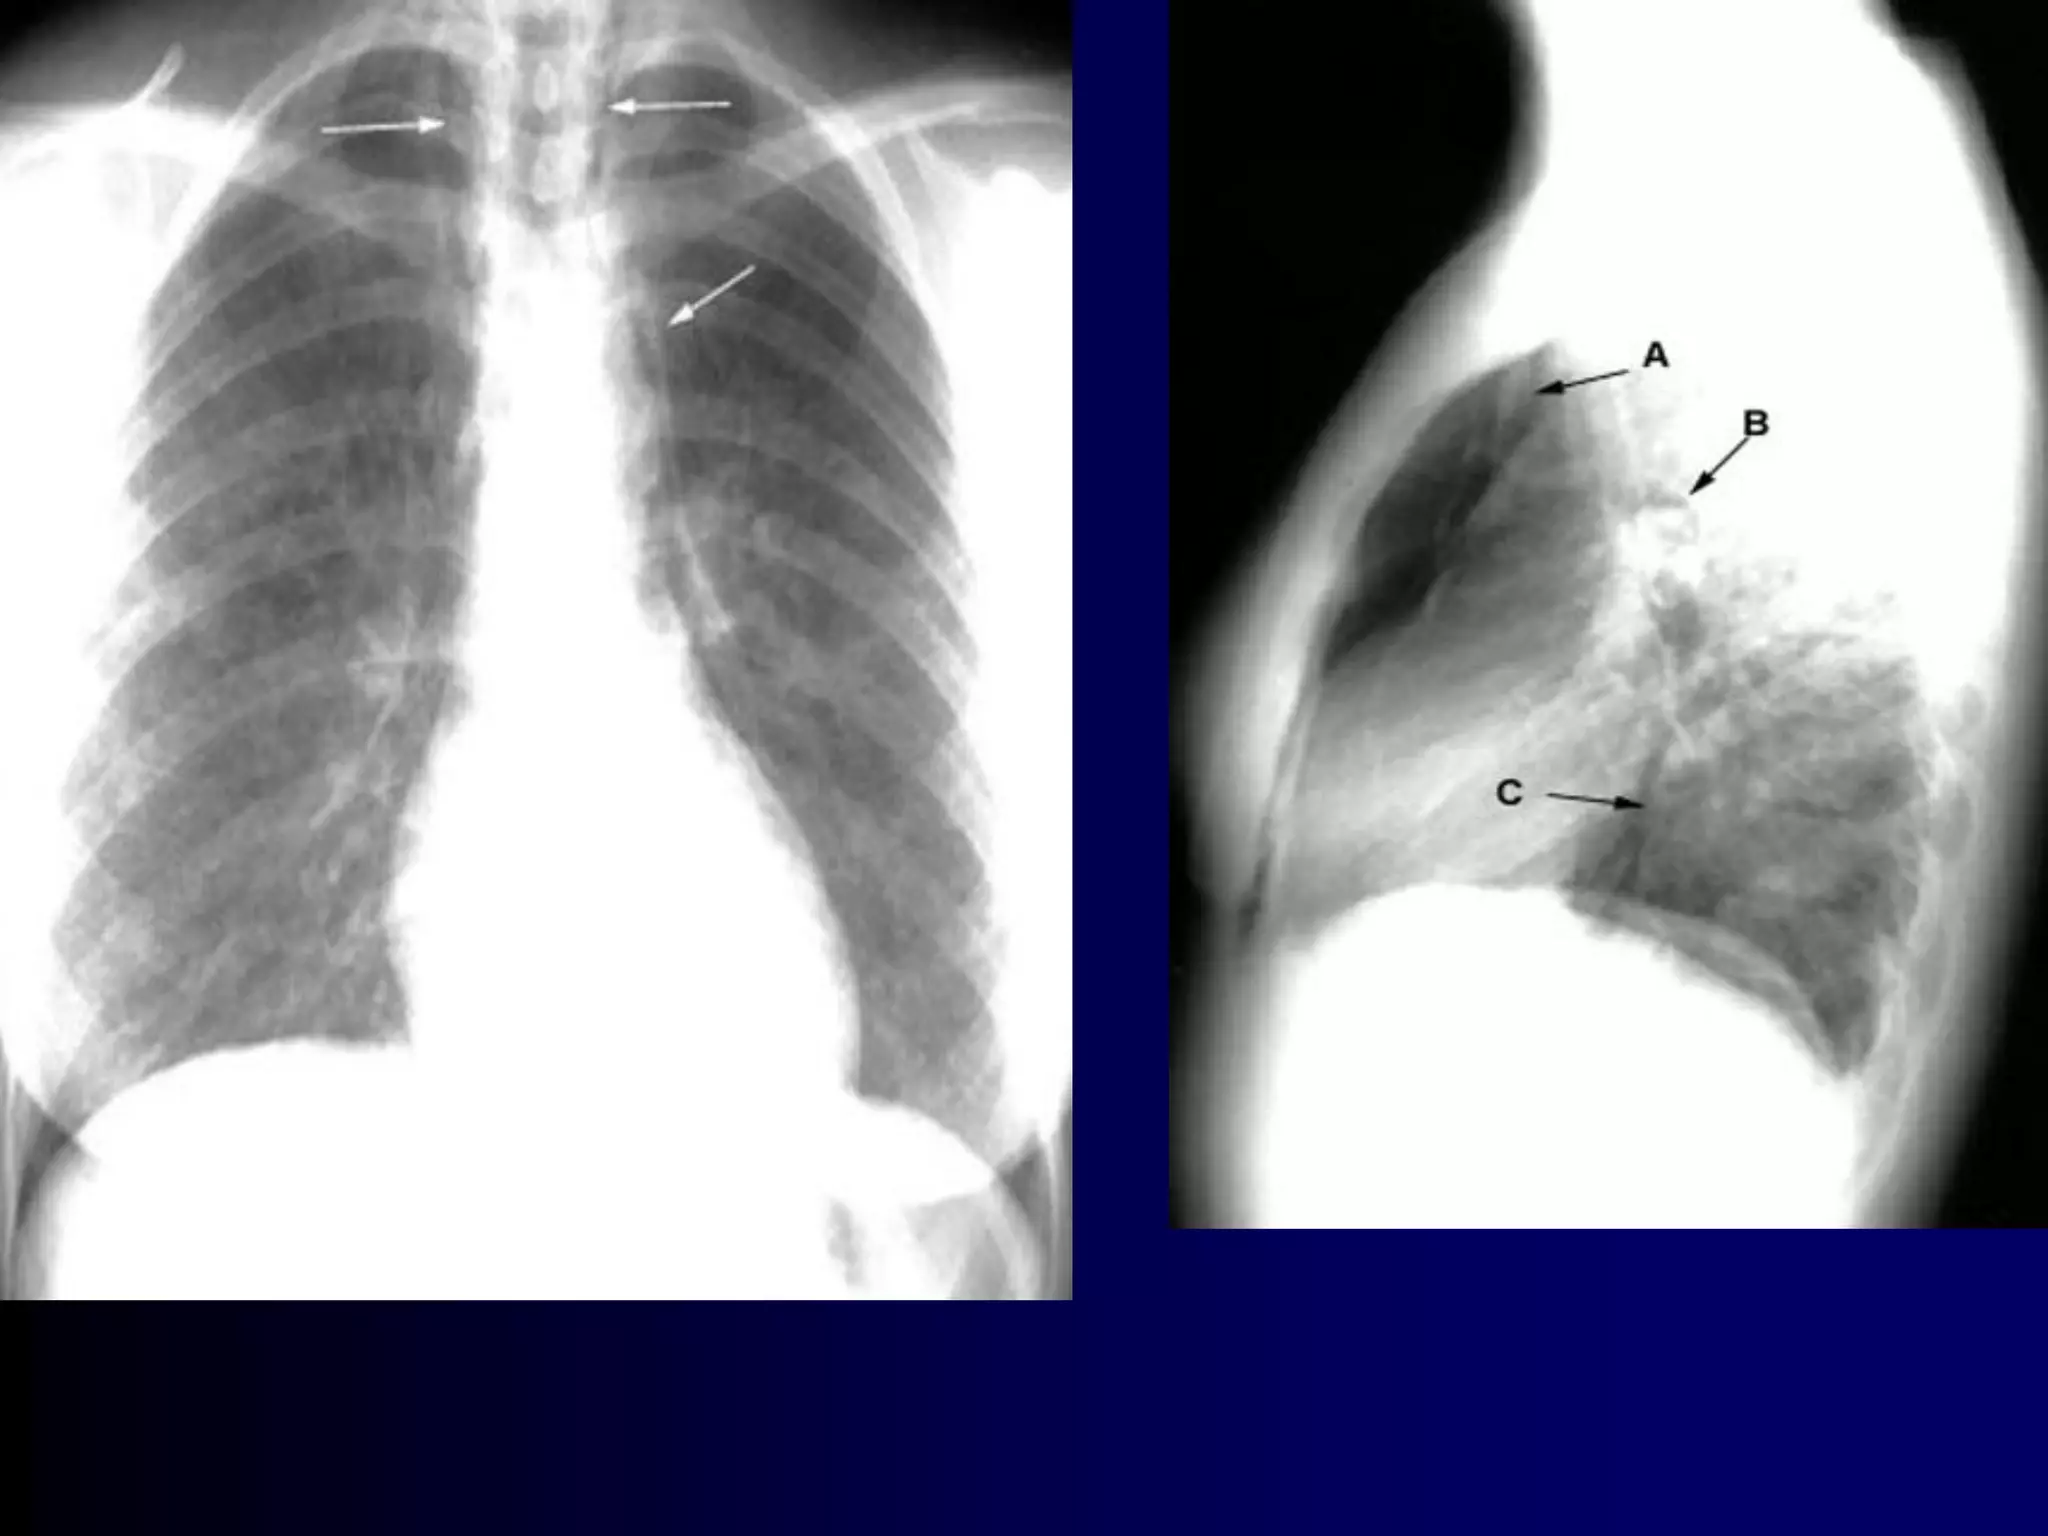

RSV Is a Common Virus Causing

Bronchiolitis in Children

 In a clinical study in Argentina, RSV was the

most common virus isolated from a sample of

children aged <5 years with acute lower

respiratory infection

0.7%6.5%6.8%

7.8%

78.2%

RSV

Adenovirus

Parainfluenza

InfluenzaA

InfluenzaB

Carballal G et al. J Med Virol 2001;64:167-174

138

New viruses (Human

Metapneumovirus,

Bocca, Corona)